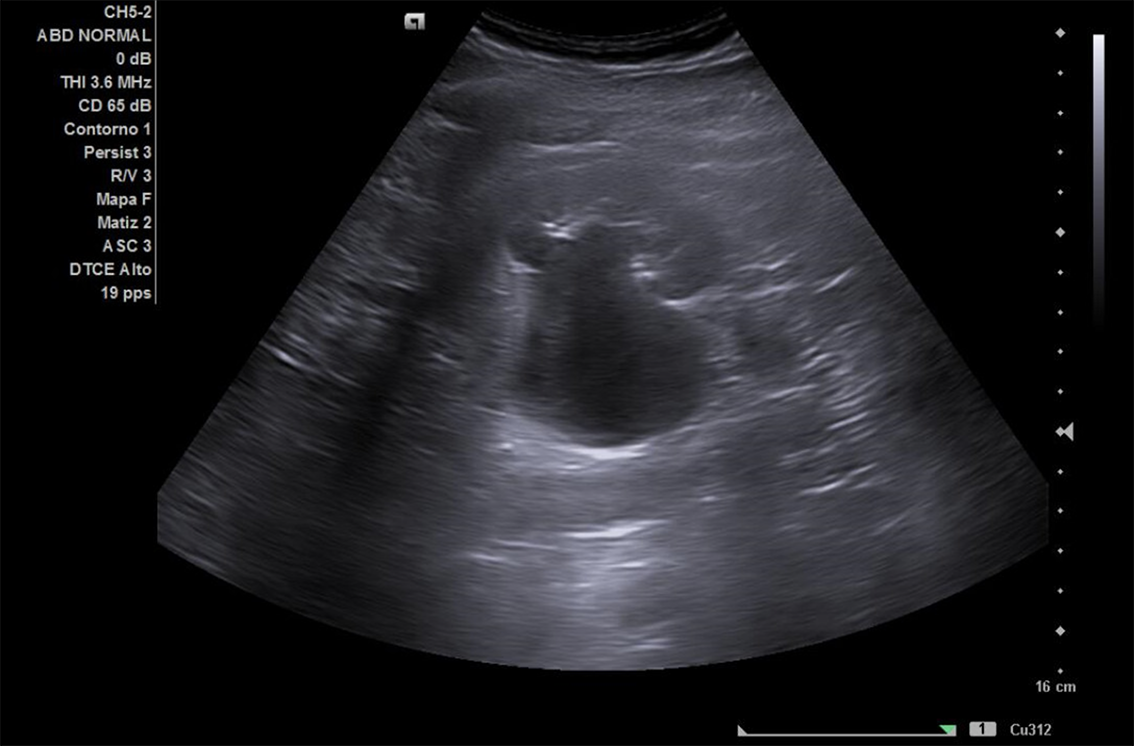

Descripción de los hallazgos ecográficos y las imágenes más relevantes para la resolución del caso

Se realiza ECO POCUS en la que se aprecia riñón derecho de morfología y tamaño normal. Riñón izquierdo con hidronefrosis grado III. A nivel de vejiga, bien replecionada se aprecia masa a nivel de pared izquierda adyacente a unión ureterovesical de 1.8 x 2,7 cm Ausencia de jet izquierdo.